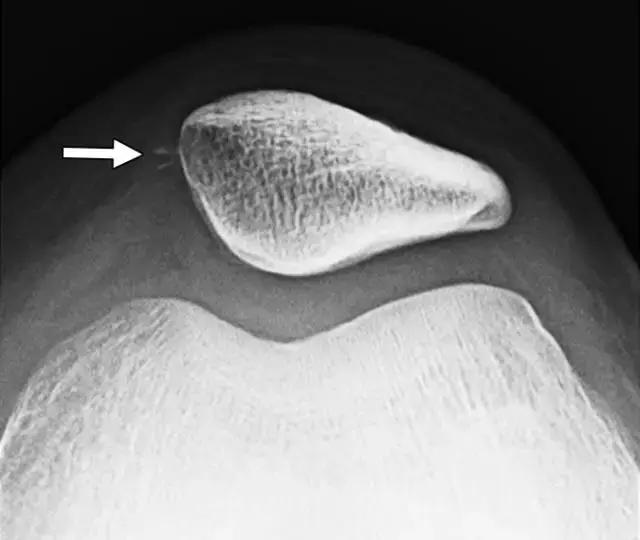

外侧髌骨脱位是一种常见的膝盖损伤,但在多达45-73%的病例中可能无法识别,并且如果没有得到适当的治疗,携带50%的复发风险[46-48]。 髌骨经常在脱位后立即重新定位,因此患者经常不知道其受伤的确切性质,身体检查由于疼痛和保护而具有挑战性。 射线照相结果通常是正常的,但是邻近髌骨中间边缘的小骨片的存在是损伤真实性质的重要线索(图9A)。 小片段表示在内侧髌韧带,所述髌内侧支持的一部分并抵靠髌骨的横向运动的初级韧带约束的髌骨附件的撕脱骨折。

图 9A -14岁的女孩患有髌骨撕脱性骨折。髌骨轴位片显示沿内侧髌骨的小骨碎片(箭头)。

当临床怀疑髌骨脱位时,推荐使用专用髌骨视野的膝盖放射线照片,例如轴位片。 Haas 等报道说,30%的内侧髌骨撕裂的碎片仅在专门的髌骨位置中被确认,否则将被遗漏。 一旦识别到撕裂性骨折,MRI是评估内侧髌股韧带状态以及任何相关损伤(如骨挫伤,骨软骨损伤和关节内松动体)的位置和程度的有价值的工具(图9B)。